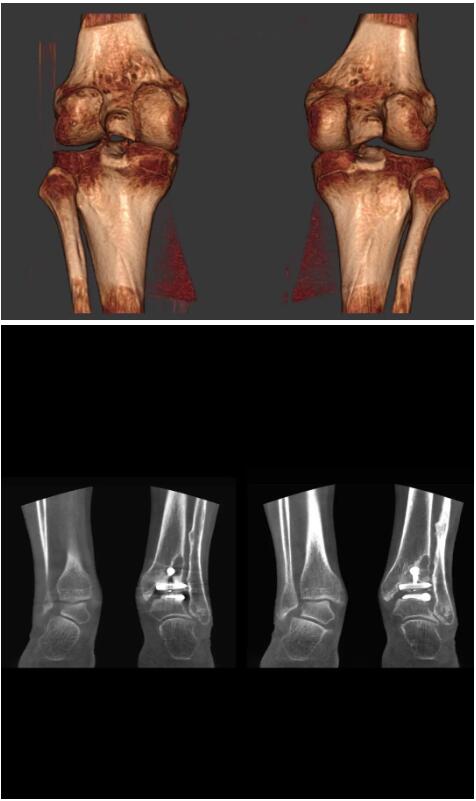

另外一款被稱為世界上最小的CT,它的重量僅300磅,不僅能夠掃查足部,還可以檢查膝蓋和上肢等。

與上面介紹的CT一樣,它同樣具有輻射低、占地空間小(23*36)的特點,隨開隨用(支持直接接入墻上的插座)。

這款CT使用非常方便,通過上下移動保持與患者的手臂或者雙腿齊平,掃描快速,僅需要30秒左右就可以完成掃查。

以下是這些“特立獨行”的CT所拍出來的圖像: